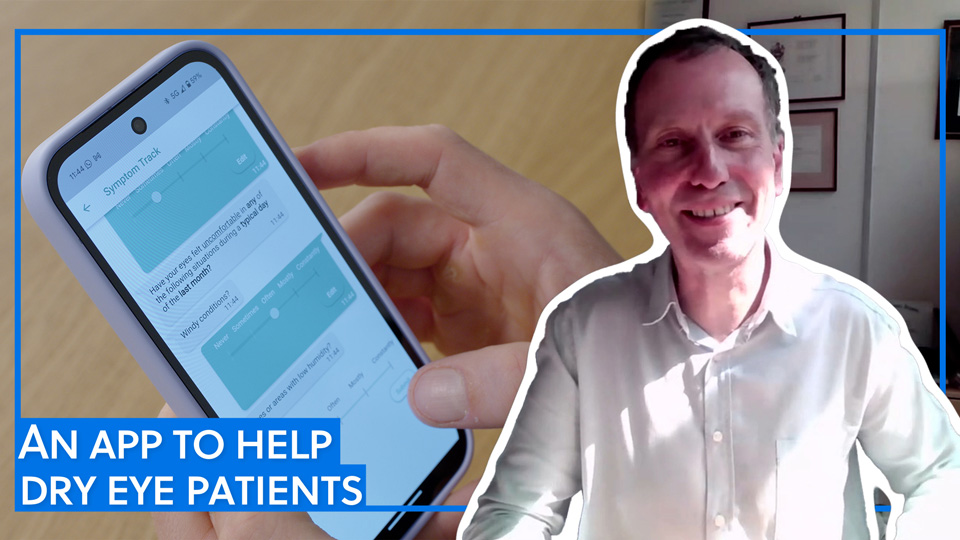

We spoke to Professor James Wolffsohn @AstonUniversity about how the MyDryEye app can assist dry eye patients in recording and managing their symptoms. Watch and learn more here: ow.ly/841f50WSjyl